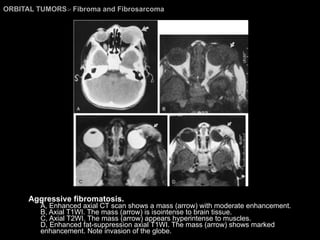

Fibroma and Fibrosarcoma Fibroma is the least common fibrous tumor of the orbit and is found mostly in young adults. It is usually encapsulated and grows slowly over several years.  It arises from the fascia of the EOMs or Tenon’s capsule in the orbit. Fibromatosis  tends to be locally infiltrative and grows rapidly, which may cause it to be considered as a low-grade fibrosarcoma. Fibrosarcoma is also rare in the orbit.  CT and MR imaging  may show a lesion with either benign-appearing or invasive characteristics.

ORBITAL TUMORS >  Fibroma and Fibrosarcoma Aggressive fibromatosis.  A, Enhanced axial CT scan shows a mass (arrow) with moderate enhancement.  B, Axial T1WI. The mass (arrow) is isointense to brain tissue.  C, Axial T2WI. The mass (arrow) appears hyperintense to muscles.  D, Enhanced fat-suppression axial T1WI. The mass (arrow) shows marked enhancement. Note invasion of the globe.